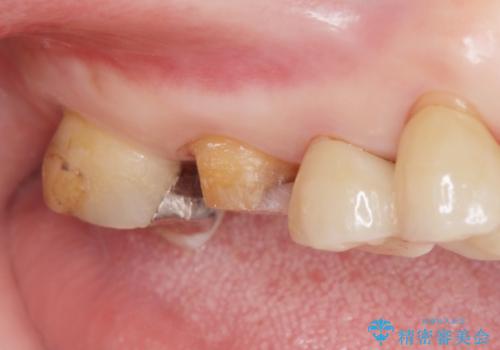

- メタルの詰め物がされている歯が欠けてしまった患者様です。

メタルを外すと中で虫歯が広がっていました。

拡大鏡下で虫歯を取り切った後、フルジルコニアクラウンにて治療しました。